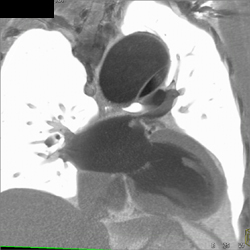

Type A Dissection